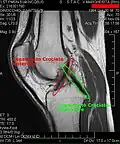

Imaging

MRI

Both anterior cruciate ligament (ACL) and posterior cruciate ligaments (PCL) are hypointense on both T1 and T2 weighted images of MRI. However, some high signal striations are often seen at the distal part of the ACL, making ACL higher intensity than PCL on MRI scans.[20]